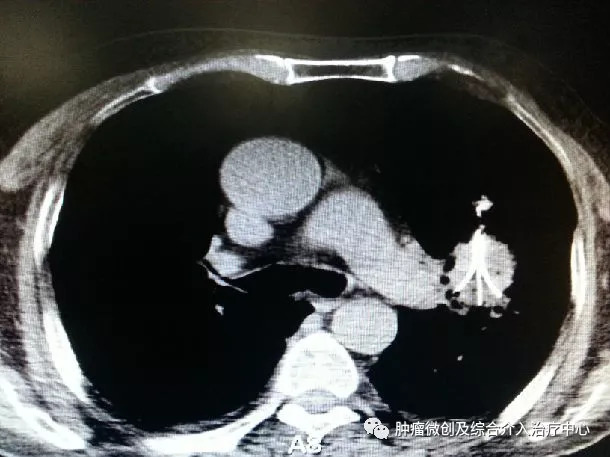

B:物理消融治疗:采用一支不到2mm的穿刺针,经皮肤直接穿刺到病灶内,通过针尖温度的变化在病灶内形成一定范围的消融区域,直接杀灭肿瘤组织,达到不开刀即能内科切除肿瘤的目的 。

C:放射性粒子植入:此方法属于近距离放疗。有别于传统外放疗受正常组织耐受剂量限制的劣势,粒子植入通过穿刺针经皮肤穿进肿瘤内部,根据一定的原则及方法,将直径不到5mm的粒子均匀放置,每颗粒子都是一个放射源,它们在肿瘤内部24小时不间断对肿瘤进行照射。使瘤内剂量高,瘤外剂量很低。效果优于传统放射治疗。